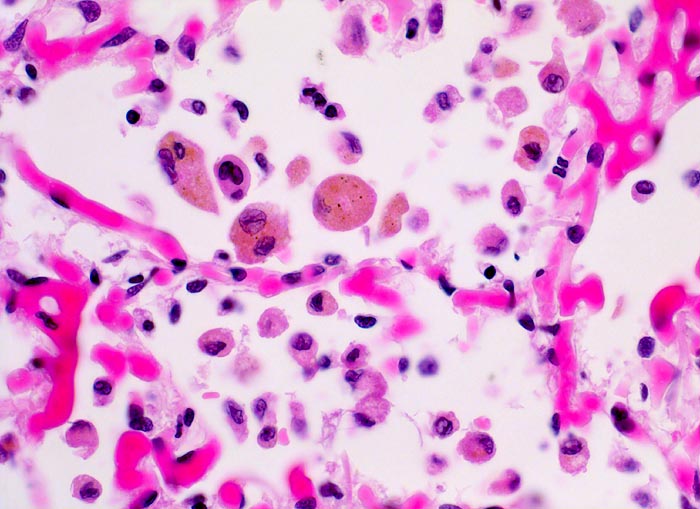

In einer frühen Phase kommt es zur roten Stauungsinduration, welche in eine braune Stauungsinduration übergeht. Die Eindrückbarkeit der Lungen ist aufgrund der Fibrosierung der Alveolarsepten vermindert. Die meist fleckförmige braune Verfärbung beruht auf der Anhäufung von hämosiderinhaltigen Herzfehlerzellen in den Alveolarlichtungen. Makrophagen in den Alveolarlichtungen phagozytieren die ausgetretenen Erythrozyten. Der Nachweis von Erythrozyten im Zytoplasma von Makrophagen spricht für eine frische Blutung. Nach 3-5 Tagen ist in den Makrophagen Hämosiderin nachweisbar. Das Hämosiderin lässt sich mittels Eisenfärbung (Berliner-Blau) zuverlässig von Staubpigment abgrenzen. Als sicheres Zeichen für eine ältere Blutung gelten >20% hämosiderinspeichernde Makrophagen in der bronchoalveolären Lavage (BAL). Die hämosiderinhaltigen Alveolarmakrophagen werden auch Herzfehlerzellen genannt, da sie gehäuft im Rahmen einer linkskardialen Stauung bei Mitralklappenstenose auftreten.

Morphologische Merkmale:

• Mediahypertrophie der Pulmonalvenen.

• Fibrosierung und Verdickung der Alveolarsepten.

• Siderinhaltige Alveolarmakrophagen (=Herzfehlerzellen).